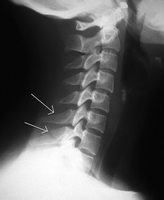

clay shoveler’s fracture